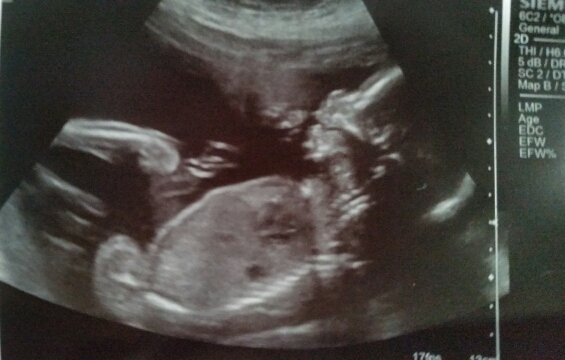

Petrified 16 week scan was wrong, 20 week scan in 2 days *UPDATE!